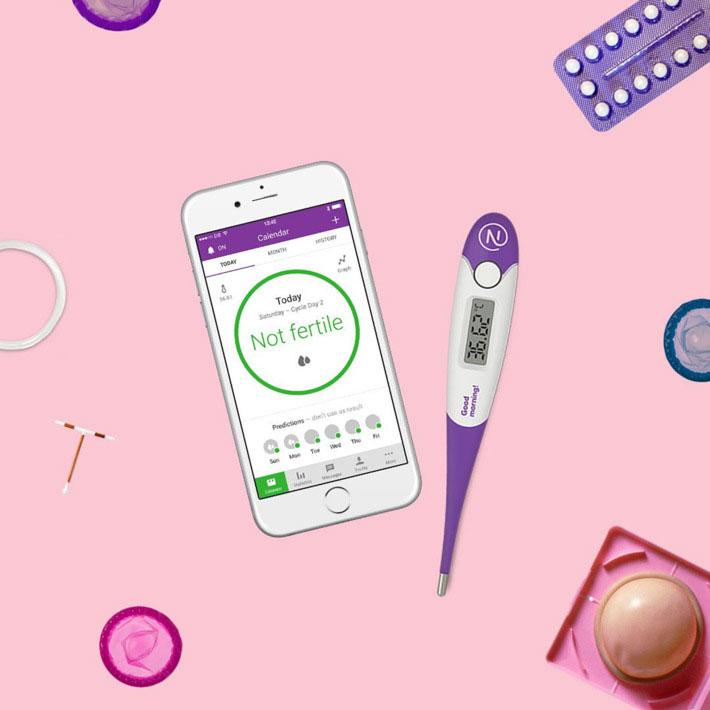

Decenas de mujeres se quedan embarazas por usar una aplicación como método anticonceptivo. | Pixabay

Decenas de mujeres han denunciado en Suecia embarazos no deseados después de usar una aplicación anticonceptiva. Concretamente, alrededor de cuarenta mujeres han explicado que utilizaban Natural Cycles, que sostiene tener entre un 93% y un 99% de efectividad, para saber si se encuentran en un día no fértil para mantener relaciones sexuales seguras.